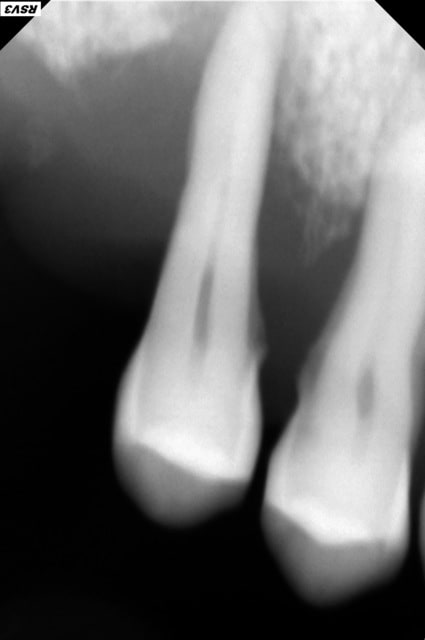

En bouche je peux voir l'apparition d'une sorte de trou sur la gencive en regard de 14 d'ou sors beaucoup de sang. Le site de l'extraction est plus ou moins refermé. La majorité de l’hémorragie viens de ce "trou". C'est pas une fistule c'est vraiment un trou de la taille d'un petit pois.

A la radio j'ai l'impression qu'on peut voir une nécrose osseuse.